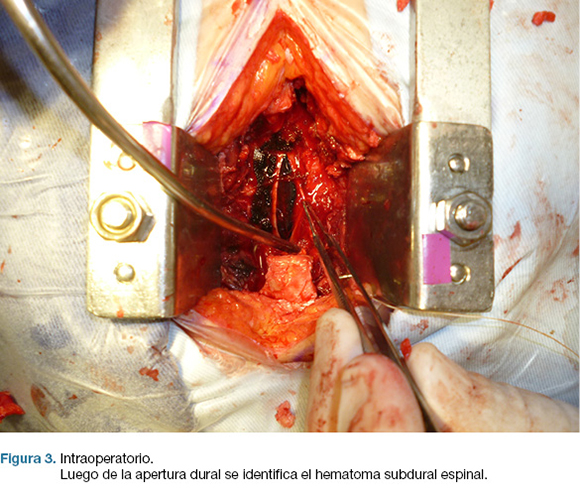

En la cirugía se realizó laminectomía T4-T6 exponiendo el saco dural. El mismo estaba tenso y azulado (figura 2) y al abrirlo, se encontró un hematoma subdural espinal, que se evacuó completamente (figuras 3).